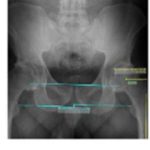

Método simple para minimizar la discrepancia en la longitud de las extremidades y restaurar el offset en la artroplastia total de cadera

Pablo D. López, Adrián G. Almada, Santiago L. Iglesias, Ignacio J. Pioli, José M. Gómez, Bartolomé L. Allende